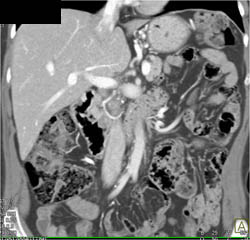

Diagnosis

GIST Tumor